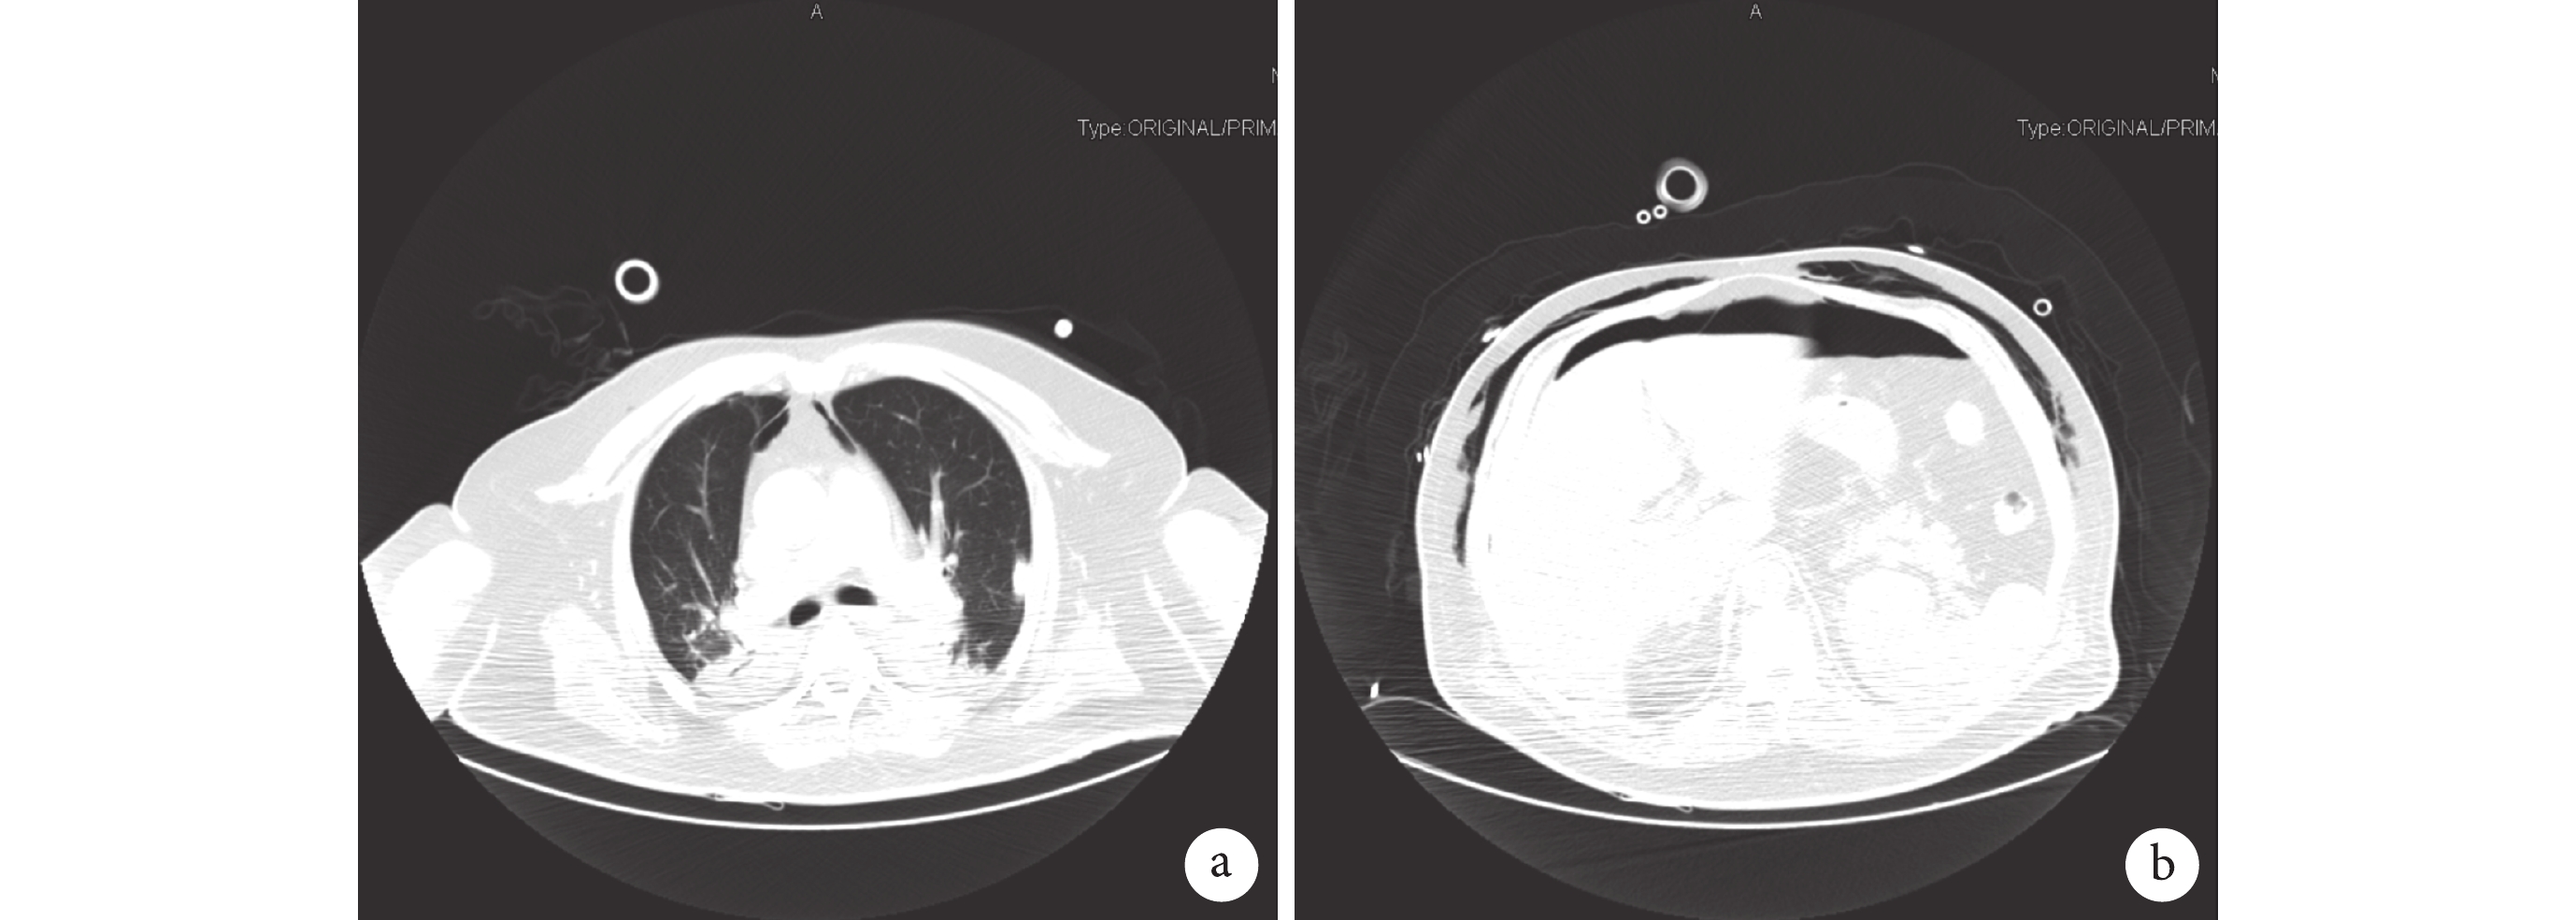

治療經過:患者對加壓給氧無反應,氧飽和度下降,加深鎮靜消除自主呼吸后氧飽和度仍未改善。為進一步明確病因,病房醫生快速將患者推往 CT 室,CT 掃描顯示:雙側頜面部、頸部、胸腹盆壁、縱隔、胸腔、腹腔及腹膜后間隙廣泛大量積氣,雙側胸腔少許積液;雙肺部分受壓不張(圖 1)。CT 檢查后轉至重癥監護室,立即床旁行左側胸腔閉式引流,引流出大量氣體。引流后 30 min 生命體征顯示脈搏 58 次/min,呼吸頻率 20 次/min,血壓 104/69 mm Hg,氧飽和度 92%(氧濃度 90%)。引流 1 d 后復查 CT 顯示:① 右側胸腔、縱隔少許積氣;腹腔大量游離積氣,腹膜后少許積氣;雙側胸腹壁、頸根部皮下軟組織腫脹、少許積氣。② 雙側胸腔積液鄰近肺組織不張,左側胸腔內見引流管影。③ 雙肺散在條索、斑片影,雙肺散在慢性炎癥(圖 2)。引流 9 d 后患者生命體征平穩,拔除氣管導管,無創呼吸機輔助,床旁纖維支氣管鏡檢查示氣道通暢,未見明顯異常。1+ 個月后患者好轉出院。

a. 雙側胸壁廣泛大量積氣;b. 雙側胸壁、縱隔、胸腔廣泛大量積氣,雙肺部分受壓不張